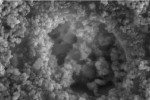

SEMs of the C-1-treated dentin are shown in Figure 4. The presence of small particles, partially covering the surface and occluding some of the tubules, can be seen (Figure 4a). The particulate nature of the deposit in this SEM is readily seen in the close-up image (Figure 4b). It contrasts with the coherent deposit seen in Figure 2 and Figure 3, resulting from treatment of dentin with AHECS.

EDX analysis of the C-1-treated surface indicates the presence of significant quantities of titanium dioxide, which is present in the control formulation. Interestingly, no silica can be detected. There are also calcium and phosphate peaks, which are from calcium phosphate mineral, which is in the underlying dentin. This calcium phosphate in the dentin is in the form of calcium-deficient HAP as shown by a calcium-to-phosphorous ratio of about 1.5.

These results show that, while only AHECS deposits a coherent layer of calcium phosphate mineral onto the surface of the dentin, C-1 deposits many insoluble particles onto the dentin and into the tubules. While the two deposits appear very different, both effect a reduction in the permeability through dentin when evaluated using the Pashley cell.